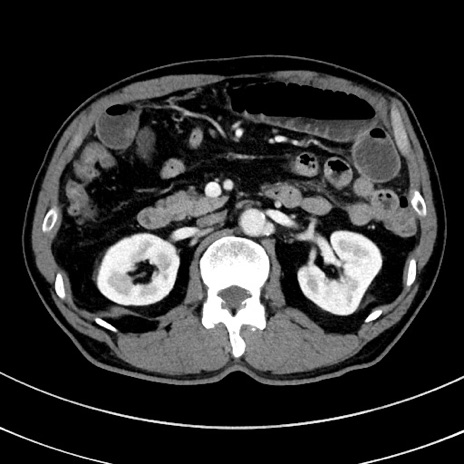

症例8(横断像)

【症例】 60歳代男性

【主訴】 黒色吐物

【現病歴】 4日前から嘔気自覚、2日前の朝食後にも嘔気あり、自分で手で嘔吐反射起こし嘔吐したところ血が混ざっていたため受診。

【既往歴】 5年前汎発性腹膜炎を伴う急性虫垂炎で手術、高血圧、前立腺肥大症、高脂血症

【身体所見】 腹部正中に手術癩痕あり 腹部平坦・軟圧痛なし膨満感あり

【データ】WBC 8400、CRP 4.54